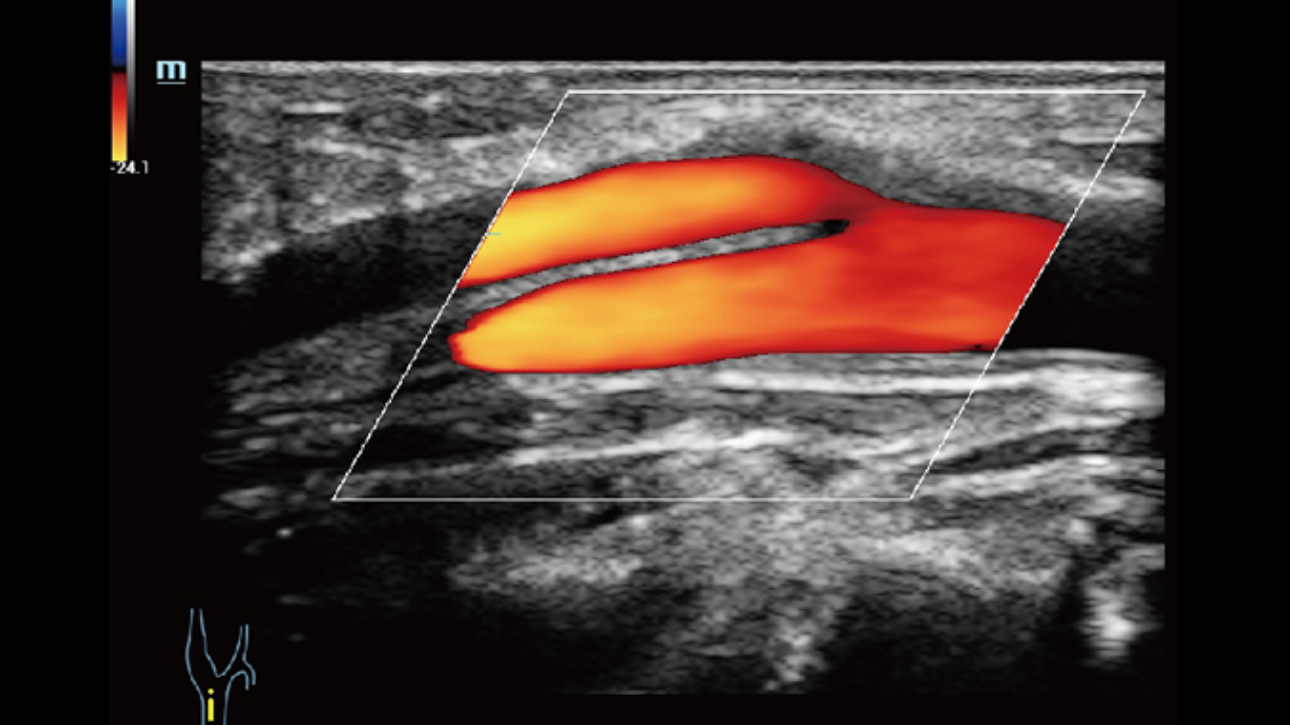

The channel data based ZST+ is an extraordinary innovation, representing an ultrasound evolution. Transforming ultrasound metrics from conventional beamforming to channel data based processing; ZST+ is able to deliver multiple imaging advances: Advanced Acoustic Acquisition, Dynamic Pixel Focusing, Sound Speed Compensation, Enhanced Channel Data Processing and Total Recall Imaging.

By transmitting and receiving a relatively smaller number of large zones, Advanced Acoustic Acquisition extracts more information from each acquisition, 10 times faster than a conventional line-by-line beamforming method.

Dynamic Pixel Focusing technology allows the Resona 6 to achieve extreme uniformity in pixel level throughout the whole field of view. Now there's no need to adjust the focal positions to achieve uniformity across patient exams.

By retrospectively analyzing complete channel data stored in channel data memory, the Resona 6 is able to intelligently choose the optimal sound speed to improve image accuracy even with tissue variation, allowing for adaptive tissue-specific optimization.

Channel data based ZST+ provides Enhanced Channel Data Processing for greatly improved imaging clarity. By multiple and retrospective channel data processing, it makes the best use of acoustic information for image improvement.